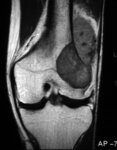

Ressonância nuclear magnética (RNM), incidência coronal; osteossarcoma do fêmur distal mostrando sinal de baixa intensidade; imagem ponderada em T1; também é visualizada extensão tumoral real intraóssea e extraóssea

Do acervo do Dr. Michael J. Klein e da Dra. Luminita Rezeanu